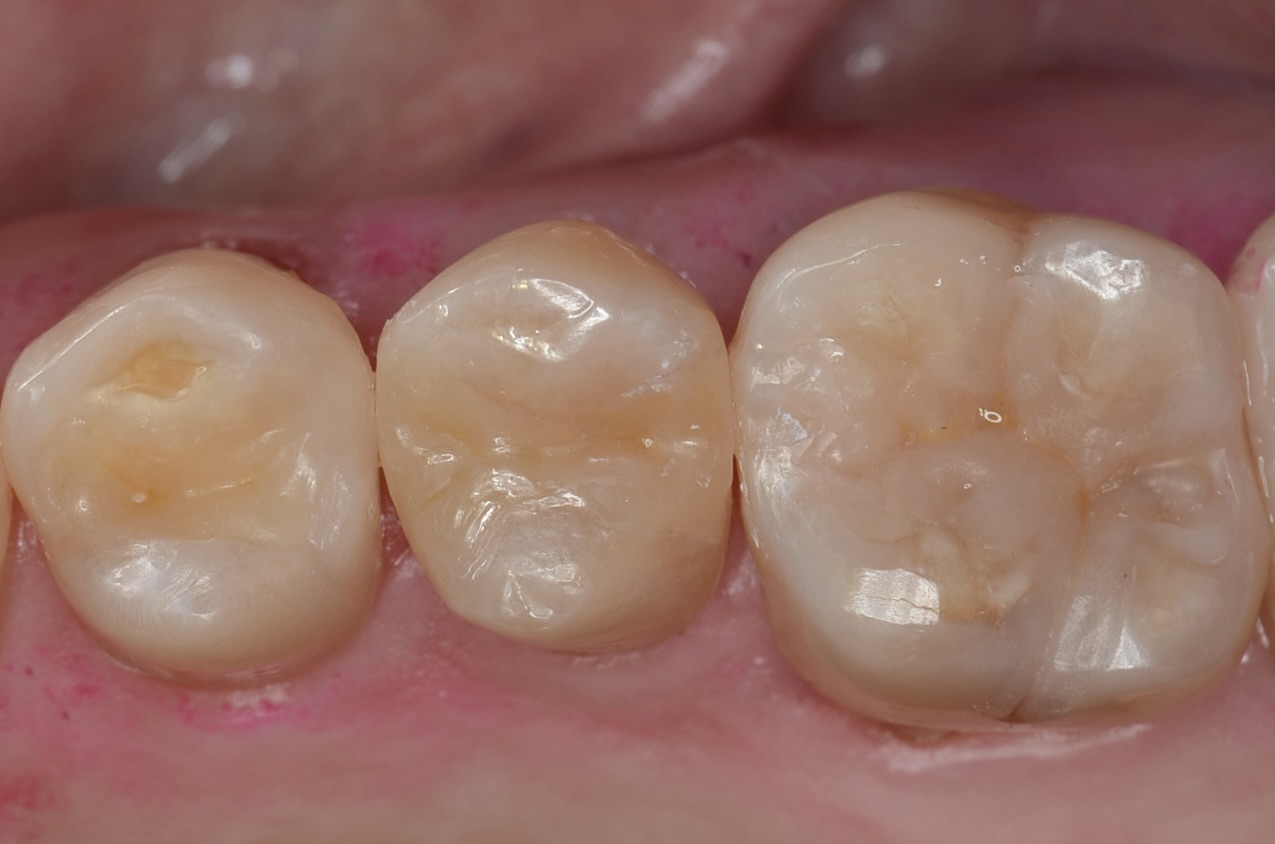

After

6番ダイレクトボンディング

5番ダイレクトボンディング

4番ダイレクトボンディング

側方面観

歯頸部の虫歯も打イレクトボンディングで治療しました。 -

口蓋側面観

滑らかな曲線でフロスも引っかからないです。